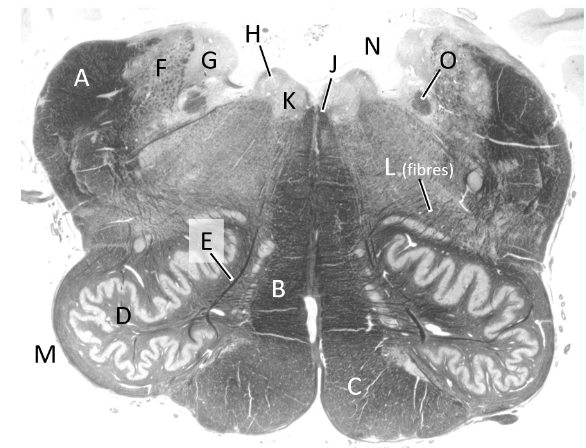

at what level is this?

mid-medulla

what is a?

inferior cerebellar peduncle

what is b?

medial lemniscus

what is c?

pyramidal tract

what is d?

inferior olivary nucleus (m)

what is e?

hypoglossal nerve fibres

what is f?

inferior vestibular nucleus

what is g?

medial vestibular nucleus

what is h?

dorsal nucleus of vagus

what is J?

median longitudinal fasciculus

what is k?

hypoglossal nucleus

what is L?

olivocerebellar fibres

what is m?

olive

what is n?

4th ventricle (m)

what is o?

solitary tract